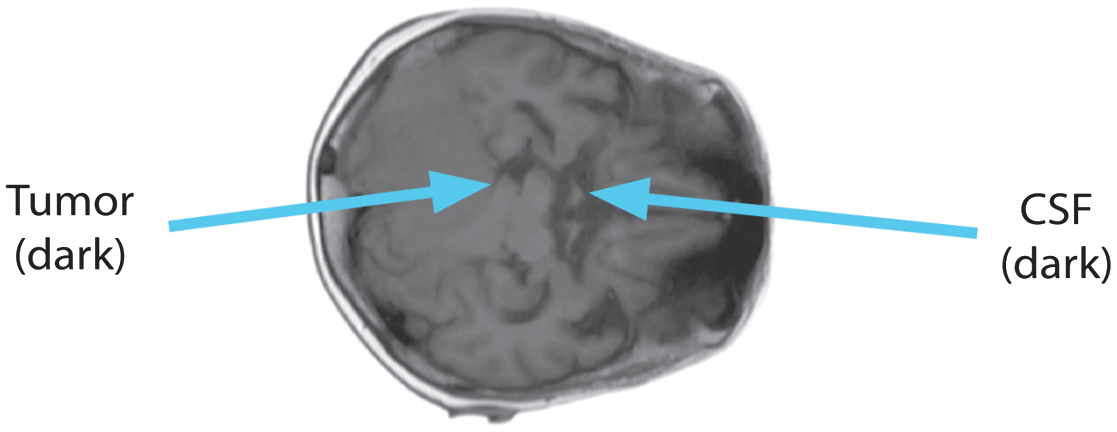

Tissue intensities mirror T1, the lengthy relaxation time, in the T1 sequence. Fatty tissue looks brilliant on T1 scans, but CSF devoid of fat looks dark. Short TE and TR periods, caused by the T1 sequence, darken the CSF. Fig. 2 shows the T1 image’s axial perspective.